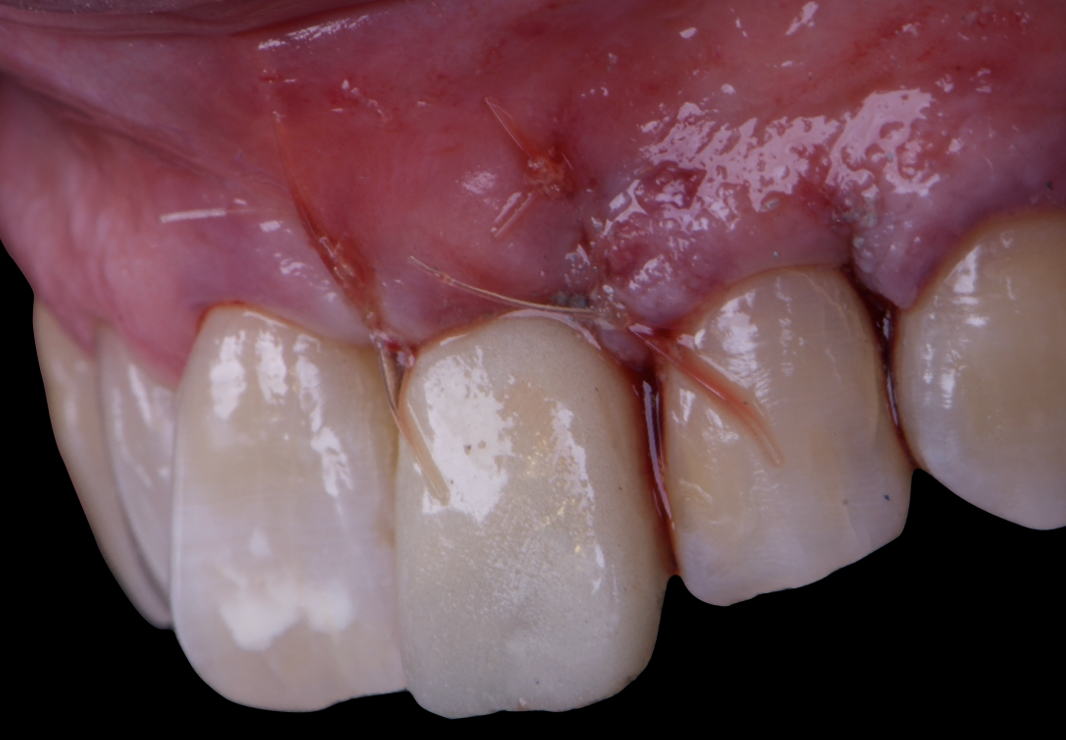

Given the significant buccal defect, guided bone regeneration (GBR) was performed simultaneously. A mixture of autologous bone and creos™ xenogain™ was applied to the defect and covered with a resorbable creos™ membrane to restore ridge width and support the buccal contour. In addition, a connective tissue graft was harvested and placed in the vestibular region to increase the thickness of keratinized mucosa. This combined approach addressed both hard and soft tissue deficiencies, providing the biological foundation for a stable and esthetic outcome.

On the same day as the surgery, an immediate-load provisional crown was delivered. This restoration was fabricated in acrylic resin and screw-retained on the implant, following the “one abutment one time” principle. The provisional crown was carefully adjusted to avoid occlusal loading while supporting the peri-implant soft tissue architecture during the healing phase.

The provisional not only satisfied the patient’s functional and esthetic demands but also played a key role in shaping the emergence profile and conditioning the gingival margin. By providing a provisional solution immediately, the patient was able to leave the clinic with a natural-looking smile, avoiding any psychological or social impact associated with tooth loss in the anterior maxilla.